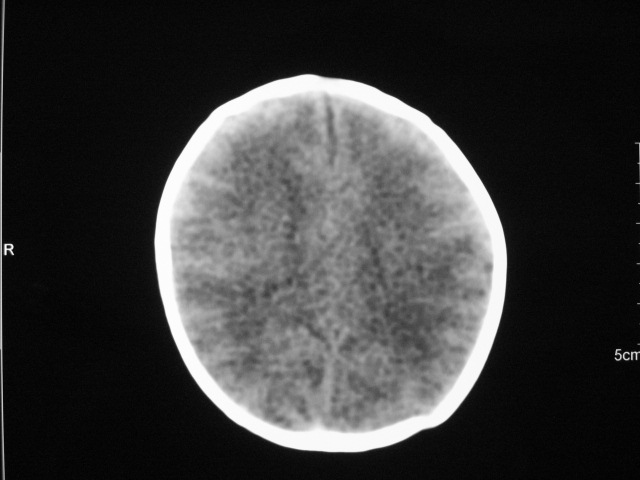

早产儿,1天,饮食呕吐,

双侧额叶见片状低密度灶,皮髓质分界模糊.患儿前囟略饱满,

支持;新生儿缺血缺氧性脑病.请密切结合临床.

患儿头颅ct示:皮质薄,髓质密度减低,脑回宽,脑沟浅,脑室系统无殊,中线结构居中,符合:早产儿颅脑ct改变。